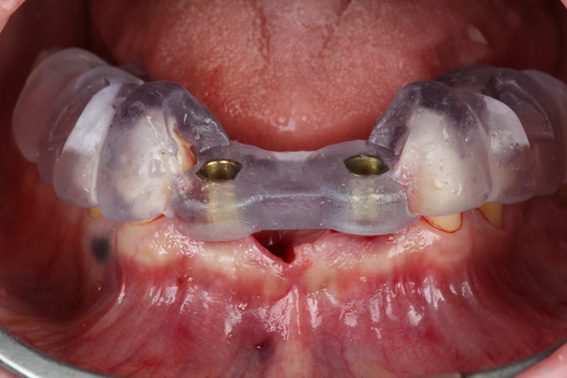

4 | Printed surgical guide in position for the start of drilling

5 | Implant Installation using the Arcsys Guided Surgery System